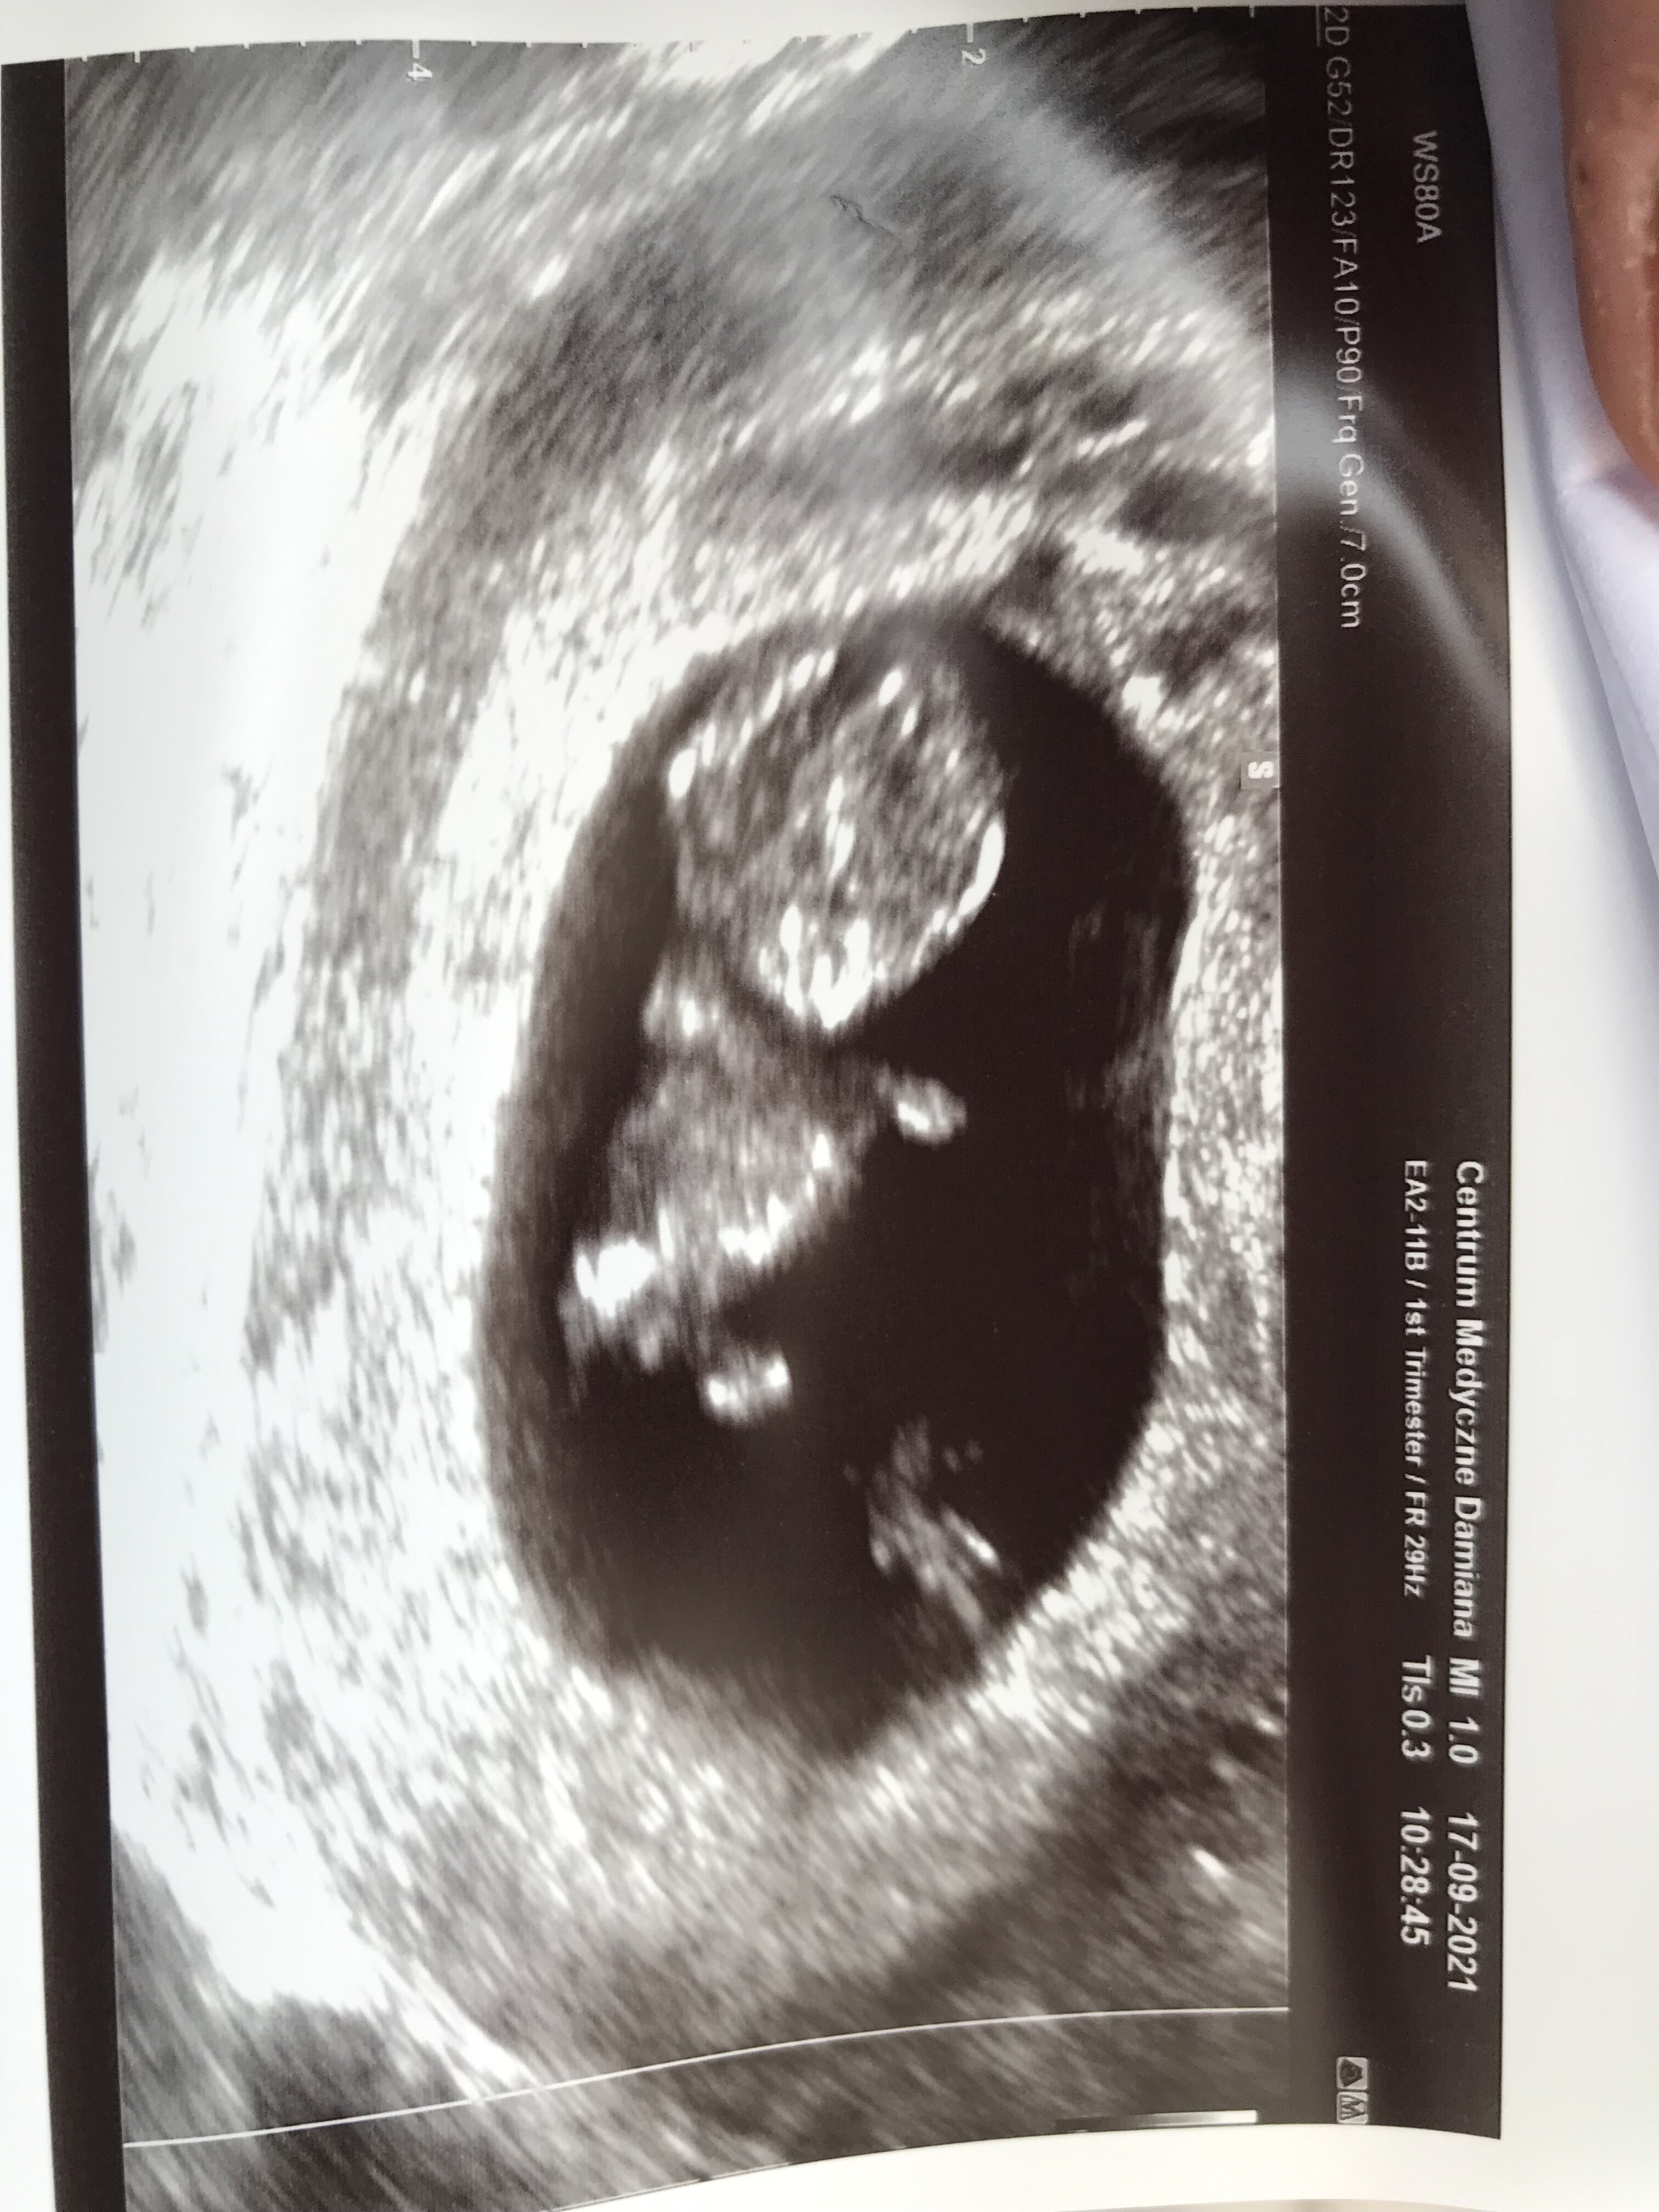

Ja w piątek byłam na wizycie, wg usg 9+5 i miałam dopochwowe. Też jestem szczupła![]()

Ale cudnie widać!! Gratuluję!Bardzo ładnieNa razie czuję się świetnie, więc mam nadzieję że u Maluszka też nadal wszystko ok